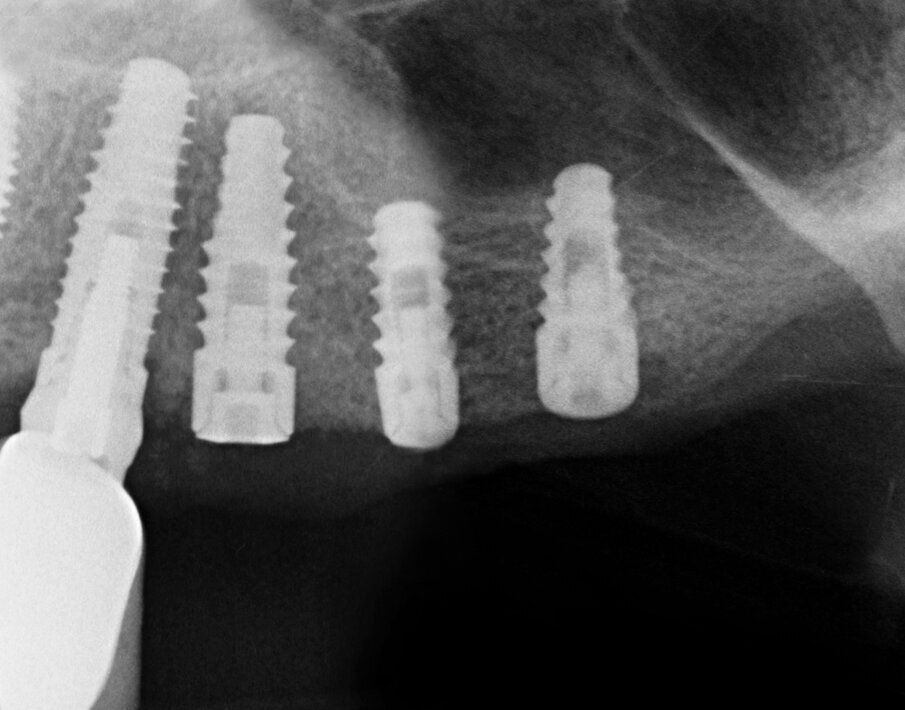

Quando le frese Densah successive avanzano nell’osteotomia, l’osso viene spinto (o densificato) verso l’estremità apicale e comincia a sollevare gradualmente la membrana di Scheneider con l’osso autologo compattato. Utilizzare sempre le frese con movimento di “pompaggio” e abbondante irrigazione, al fine di non surriscaldare l’osso. Per raggiungere una maggiore profondità verticale e il sollevamento graduale della membrana senza perforazioni si consigliano incrementi di 0,5 1,0 mm per fresa, fino ad ottenere la lunghezza e il diametro finale desiderato. Si ricorda che le frese in successione possono raggiungere un sollevamento della membrana di massimo 3 mm. Vista la scarsa qualità e quantità ossea residua del caso in questione, pur usando le frese Densah in modalità di osseodensificazione non si riesce a mantenere una integrità ossea della porzione apicale dei siti osteotomici (Fig. 5). Nei casi di incrementi superiori a 3 mm si può collocare all’interno dell’osteotomia del materiale da innesto, utilizzando l’ultima fresa con velocità di 150-200 giri/min senza irrigazione e in senso antiorario, per compattarlo all’interno dell’osteotomia. In questo caso si posizionano delle membrane di PRF all’interno dei siti osteotomici, così che la membrana di Schneider venga sollevata idrostaticamente con leggere pressioni del PRF (Fig. 6). Finita la fase di preparazione dei siti osteotomici si può procedere all’inserimento implantare a 20 giri/min e 50 Ncm di coppia (Fig. 7). Si esegue a questo punto un innesto di osso eterologo tipo “L-PRF-block”7 per incrementare il volume della zona vestibolare (Fig. 8). Sull’innesto vengono posizionate delle membrane di PRF assottigliate (Fig. 9) e una ulteriore membrana riassorbibile viene posizionata sopra il PRF per assicurare l’immobilità del tutto (Fig. 10). Si procede con l’esecuzione di scarichi di rilascio periostali, per avere un lembo privo di tensioni muscolari (Fig. 11). Infine, viene eseguita una sutura con filo 5 zeri riassorbibile monofilamento (Fig. 12). Nell’immediato post-operatorio viene eseguita alla paziente una CTCB di controllo. Come si può notare dalle sezioni della stessa, la membrana sinusale non risulta perforata, ed è sollevata sugli impianti (Figg 13, 14). Notare la neoformazione ossea apicale agli impianti a 5 mesi dall’intervento (Fig. 15).

Fig. 7 - Impianti posizionati in sede 23, 24, 25.

Fig. 13 - Sezione panorex post-operatoria: si noti il sollevamento della membrana di Schneider sugli impianti.

Fig. 15 - Controllo radiografico a distanza di 4 mesi dall’intervento.